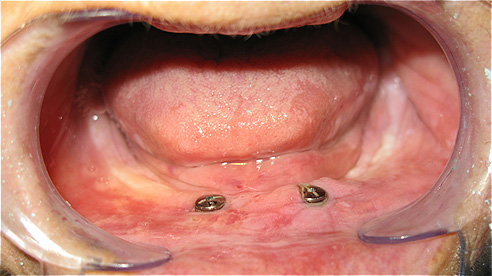

Caso 3 - Desdentado total reabilitado com prótese acrílica removível inferior, barra e clips para retenção e estabilidade

![]() |

![]() ![]() |